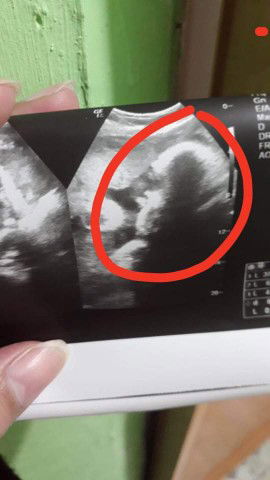

sa wakas nkapagpaultrasound din aq.. 32 weeks.. kitang kita q muka nya.. ?? baby boy .. so happy kc boy din gusto ni hubby q.. ??